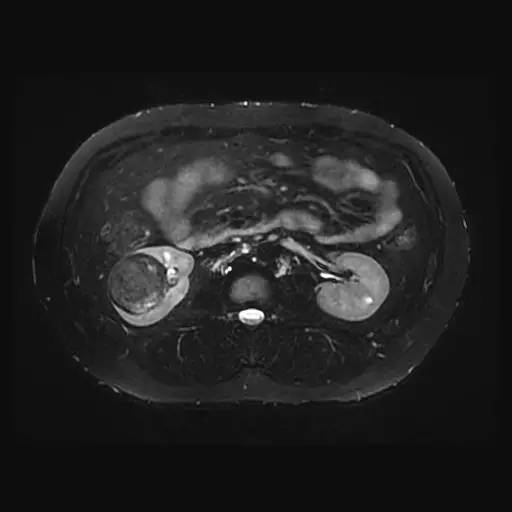

右肾中下部见类圆形约52*49*59毫米类圆形短和稍长T1、短和长T2异常信号肿块,可见假包膜,DWI呈晕环结节状稍高和稍低信号,反相位图像病变信号未见异常减低;皮质期病变未见异常强化,髓质期及延迟期持续轻度强化;病变内小部分区域未见强化。所见肝胆、胰腺、脾脏及双侧肾上腺未见异常,肝门、肾门及所见腹膜后未见异常肿大淋巴结影。

影像诊断:右肾中下部少血供肿块伴出血、坏死和囊变,考虑:恶性肿瘤,以肾癌(非透明细胞癌)可能性最大,不能完全除外表现不典型的血管平滑肌脂肪瘤。